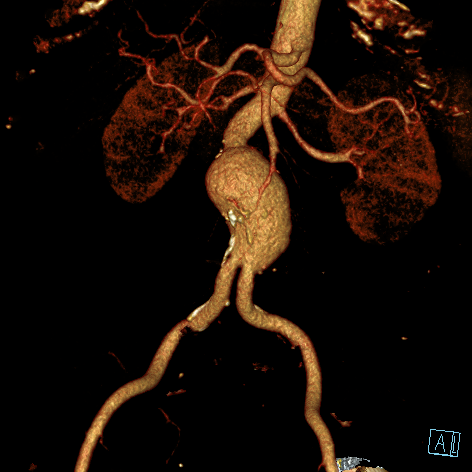

Bauchschlagadererweiterung (Aortenaneurysma)

Eine Erweiterung der Bauchschlagader kann das Risiko eines Gefäßeinrisses stark erhöhen (Aneurysma). Die Radiologie bietet hier zusammen mit den Kollegen der Gefäßchirurgie ein minimal-invasives Verfahren zur Ausschaltung des Aneurysmas an. Dies geschieht mittels Stent-Prothese (endovascular aortic repair; EVAR).